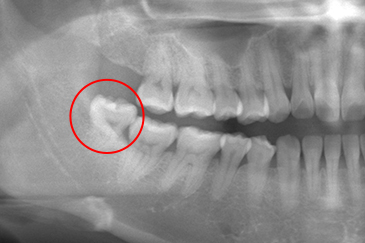

現在の治療費と異なる場合がございます。最新の治療費は料金表をご確認ください。CASE 1

事前にCT撮影を行い神経との位置関係を確認して抜歯を行いました。右下親知らずは歯ぐきの中に完全に埋まり、

また斜めに生えていた為歯ぐきを切って親知らずの頭部分を分割して抜きました。

翌日多少の腫れが見られましたが痛みも痛み止めを飲めば過ごせる程度で出血はほとんどありませんでした。

抜歯前

抜歯後

基本情報

| 年齢・性別 | 24歳・女性 |

|---|---|

| 主訴 | 右下の親知らずが抜きたい |

| 治療内容 | 完全埋伏抜歯 |

| 治療期間 | 60分 |

| 治療費 | 約8,000円 |

| リスク・副作用 | 2〜3日は腫れと痛みがある。 必要に応じて抜歯を2回に分けて行う場合がある。 |